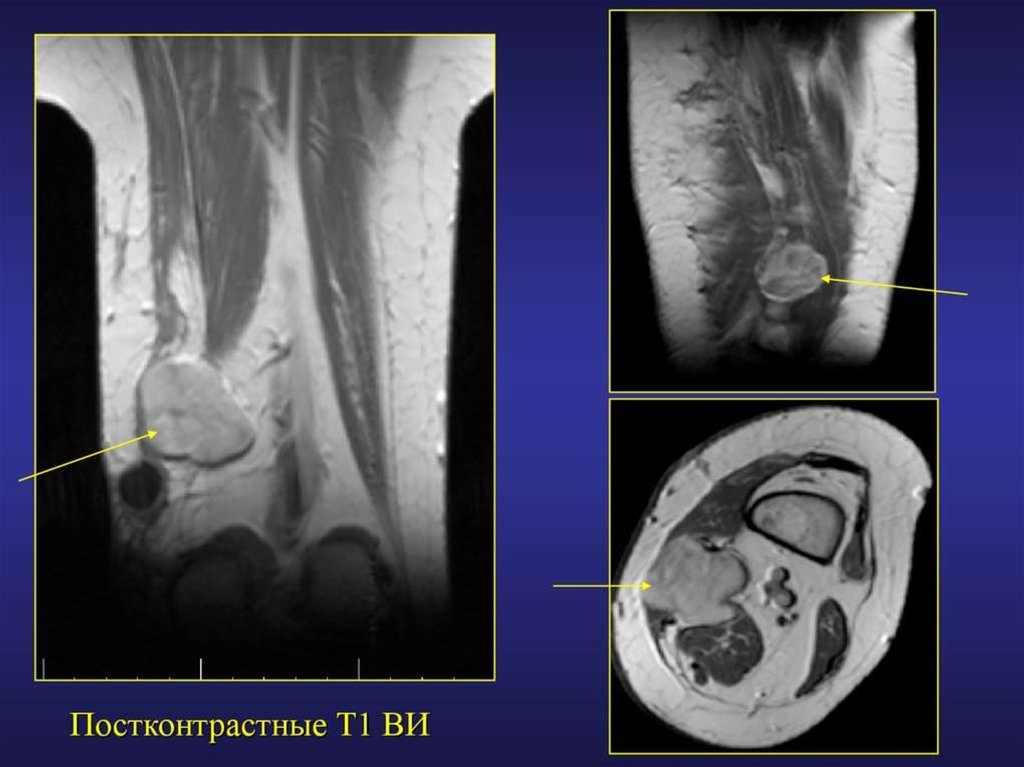

МРТ диагностика повреждений и заболеваний мягких тканей